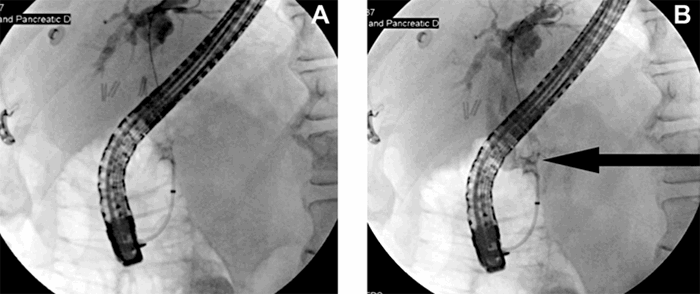

Division of the portal vein below the fistula was not a feasible option because this portion of the portal vein was necessary to provide the new liver with portal flow. The defect was then primarily repaired via the posterior wall of the common bile duct. The repair was completed with 4-0 Prolene suture in a running fashion while maintaining simultaneous manual compression (Figure 3 and Figure 4). Carefully avoiding narrowing of the portal vein during the repair, the common bile duct was transected distal and proximal to the site of the repaired fistula and oversewn with 4-0 Prolene suture. The anterior wall of the common bile duct was then excised, and the posterior wall left behind, attached to the native portal vein.

Figure 3. Porto-biliary fistula exposed prior to repair. ©2019 Amanda Frataccia. Image used with permission

Figure 4. Porto-biliary fistula repair with simultaneous liver transplantation. ©2019 Amanda Frataccia. Image used with permission